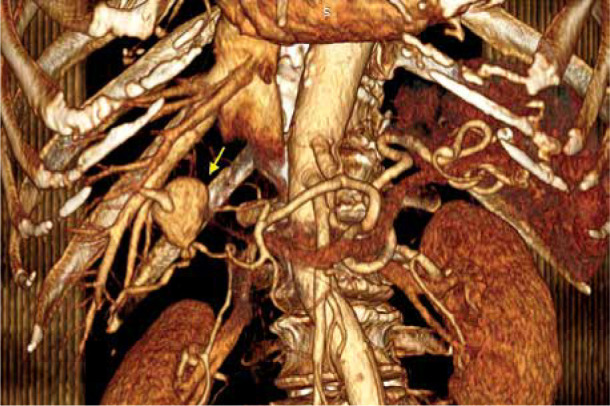

一名系统性红斑狼疮血管炎患者的右肝动脉分支肝内动脉瘤。

Intrahepatic aneurysm in a branch of the right hepatic artery in a patient with vasculitis due to systemic lupus erythematosus.